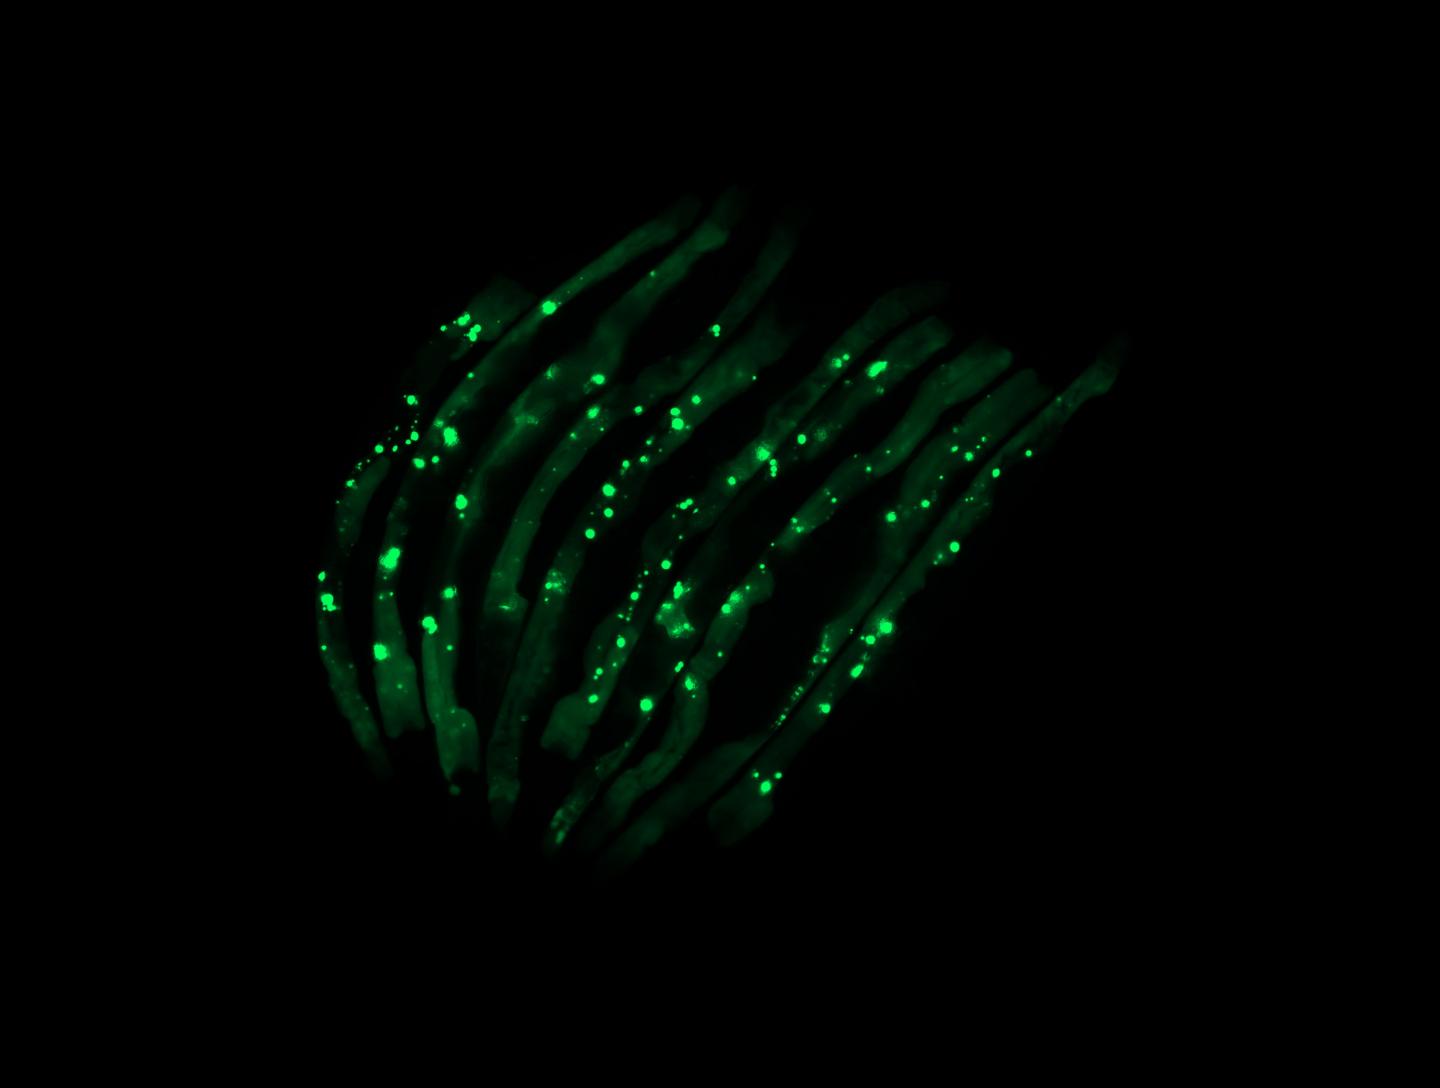

"That is, in fact, what we observed. We have a way of marking the aggregates so they glow green under the microscope. We saw that worms colonized by certain bacteria species were lit up with aggregates that were toxic to tissues, while those colonized by the control bacteria were not," Czyz said. "This occurred not just in the intestinal tissues, where the bacteria are, but all over the worms' bodies, in their muscles, nerves and even reproductive organs."